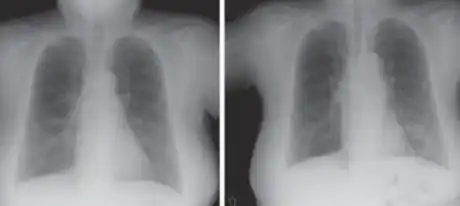

-

a,b)Hollow lesion in the lower left lung field was diagnosed as a lung abscess -